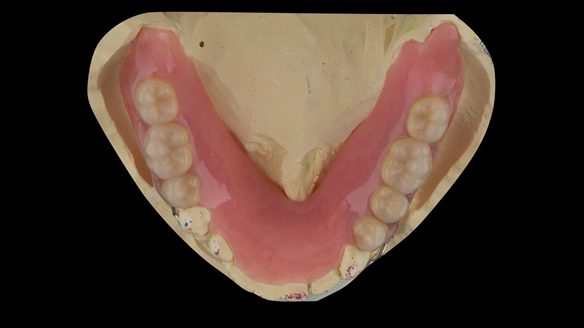

This newsletter describes in step by step detail the transition from acrylic based immediate dentures to metal based definitive dentures.

- Definitive dentures (Mk 2) – complete upper metal reinforced and lower cobalt chromium based partial of hygienic Scandinavian design to be made 9 - 12 months after extractions of all upper teeth and LR5 and LL4